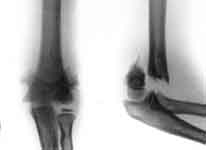

1.Перелом плечевой кости.

2.Остеосинтез с помощью аппарата Веклича.

3.Результат лечения.